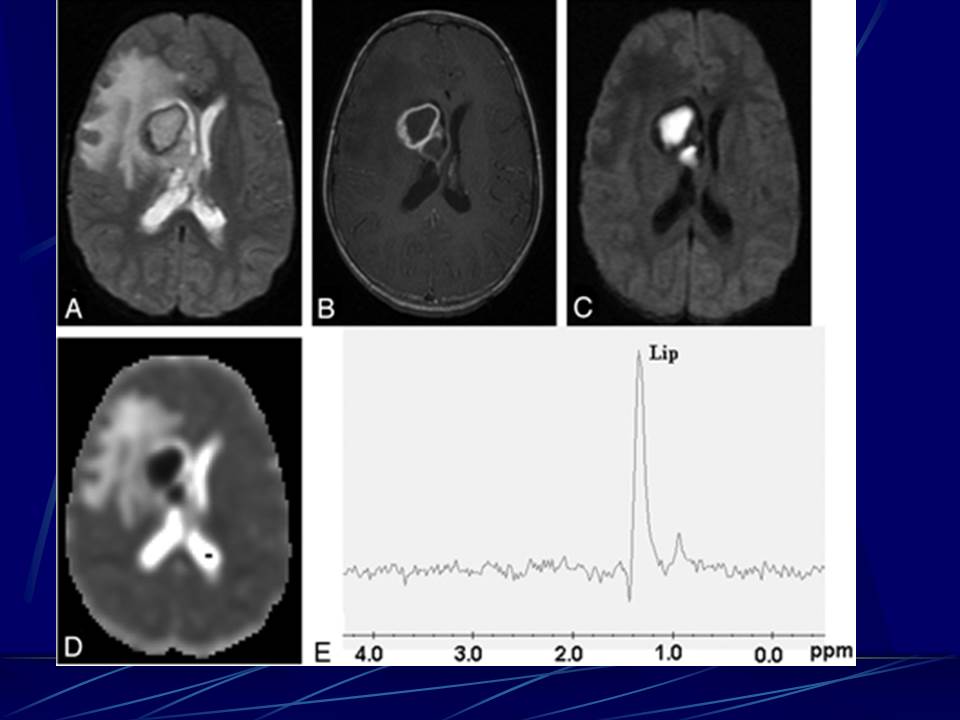

肺部真菌感染影像学分析